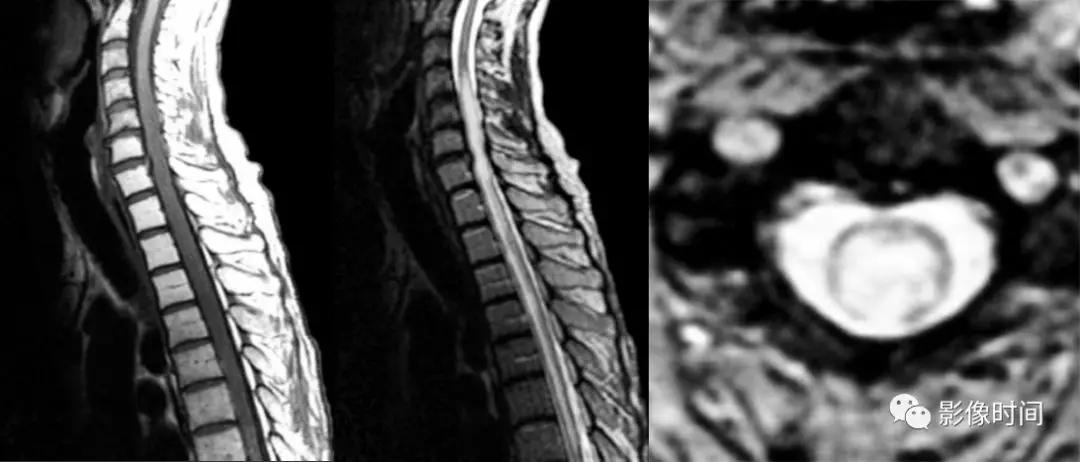

硬脊膜动静脉瘘 (spinal dural arteriovenous fistula,SDAVF):供应脊膜或神经根的细小动脉,在椎间孔处穿过硬膜与脊髓引流静脉相通,导致脊髓回流受阻。病因不明,成人-老年人胸腰段多见,缓慢起病,进行性加重。

MRI:

-

矢状位 T2WI 发现长节段高信号

矢状位 T2WI 脊髓周围流空低信号血管影

部分可见强化,提示血脑屏障破坏

脊髓内长节段T2WI高信号,髓周可见多发点状流空血管,增强扫描出现强化